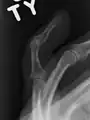

Le diagnostic est généralement basé sur les symptômes et confirmé par des radiographies[1]. La lésion peut être accompagnée d'un œdème et d'une ecchymose[3].

Un doigt en maillet sans fracture associée